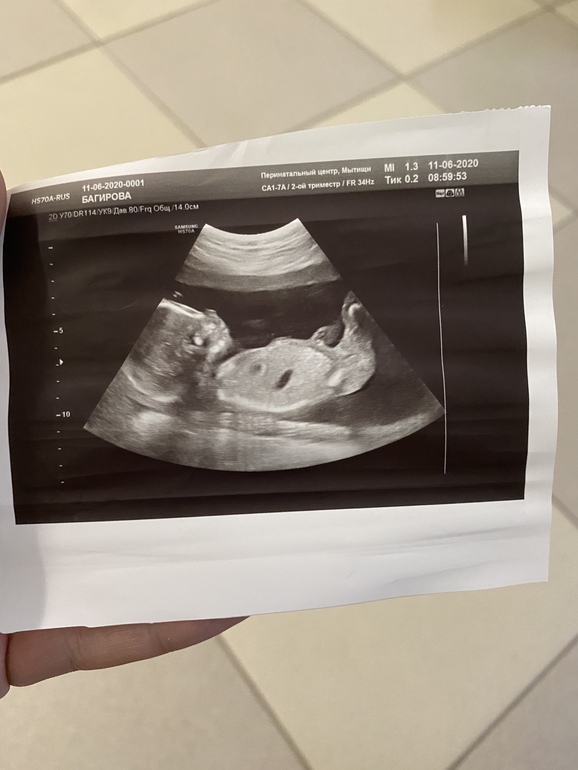

2 скрининг ,Девушки я вас умоляю , 😔объясните мне что на бумажке написано 😔😔😔😔😔

Второй скрининг 19 недель ,

Врожденный порок сердце, дуга аорты в право развёрнута 18,4 недель

Здравствуйте, девушки прощу вас дайте мне совет, что это значит ? У кого так было ? Это 100 % диагноз ? Живут ли такие детки ? ☹️☹️☹️☹️☹️☹️Всем спасибо за ответы